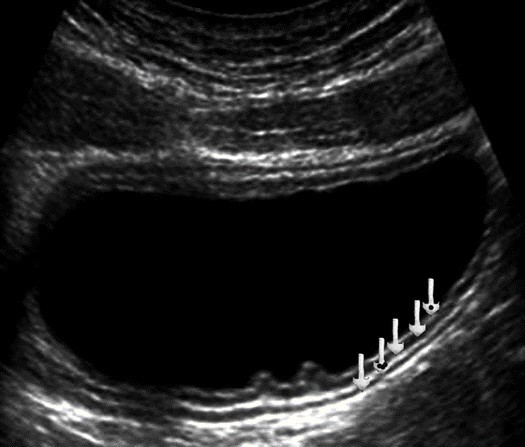

Color Doppler mode was used to assess the nature of the gastric wall lesion in pathologically thickened areas. This method allows the recording of blood flow in the altered areas and using the degree of vascularization to differentiate gastric cancer and other benign changes. Usually in a normal gastric wall it is not possible to visualize the vessels.

Among the 61 patients, pathological vascularization was detected in 42 (68.8%) cases. Of these, all 4 (6.5%) patients with gastric cancer were stage T4 and 38 (62.3%) were stage T3. In 13 cases, vascularization was weak, in 24 cases - moderate, and in 5 cases - enhanced.

Among the 61 patients, pathological vascularization was detected in 42 (68.8%) cases. Of these, all 4 (6.5%) patients with gastric cancer were stage T4 and 38 (62.3%) were stage T3. In 13 cases, vascularization was weak, in 24 cases - moderate, and in 5 cases - enhanced.

Weak vascularization was manifested in the form of a single point color vascular signals, the moderate vascularization - in the form of linear color vascular signals and the enhanced vascularization - in the form of wide color areas inside the tumor (Figure 16, Figure 17).

Figure 16.Distal gastric carcinomas of diffuse infiltrative form of T4 stage. Despite the large size of the tumor the vascularization is manifested in the form of single point color vascular signals.

Figure 17.Gastric carcinomas of infiltrative ulcerative form of Ts stage. Despite the small size of the tumor the vascularization is manifested in the form of wide color areas inside the tumor.

Metastasis to the regional lymph nodes was diagnosed in 52 cases. Ultrasonographically, this was detected in 37 (71.2%) cases. Sonographic features of lymph node metastatic lesions are: an increase in their thickness, a decrease in echogenicity, deterioration or lack of differentiation of the peripheral and central parts of the nodes, recording of color vascular signals inside the nodes (Figure 18, Figure 19).

Figure 18.Metastasis to the retroperitoneal lymph node in gastric cancer of the antrum of T3 stage. The longitudinal size of the lymph node is increased to 5 cm, the echo is significantly reduced, along the periphery of it is visible color vascular signals in tissue Doppler mode.

Figure 19.Metastatic affected lymph node in gastric cancer of the anterior wall of the stomach of stage T4. Significantly enlarged lymph node, echogenicity reduced, large vascular signals in color Doppler mode visible in the center.